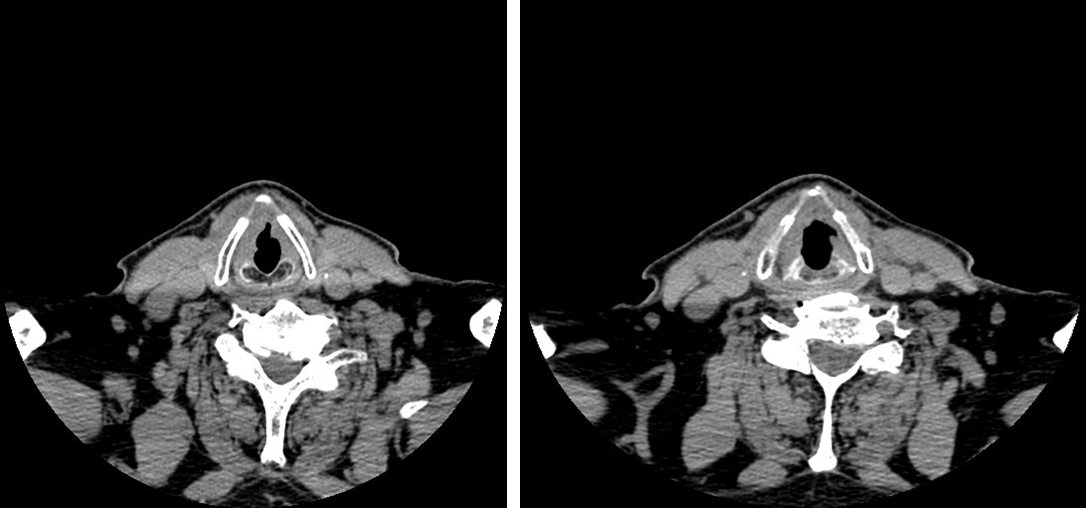

Diagnosis: Laryngeal Cancer - T4N0M0

CT scan 30.11.2015: tumor mass of the right vocal and vestibular folds, circumferential spread to the left side of the glottis, involving of the left fold,crawling under the subglottic region. Single remarkable features of the cartilage involvement.